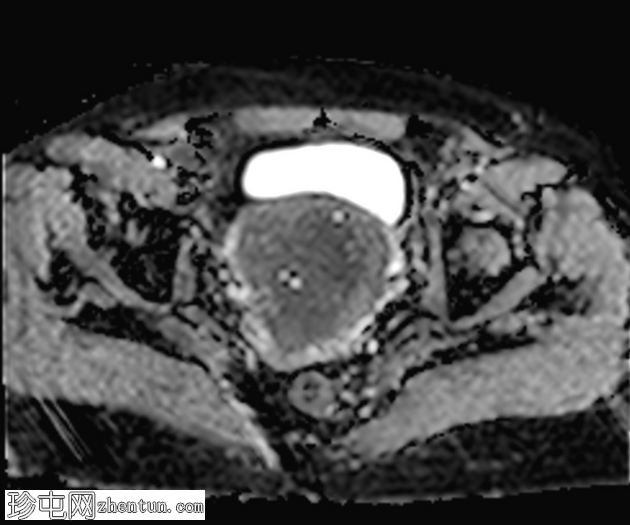

轴位

T1加权像

子宫增大,交界区弥漫性增厚,厚度约2.5 cm,边界模糊,在T1加权像和T2加权像上均可见无数点状高信号灶,提示出血灶。